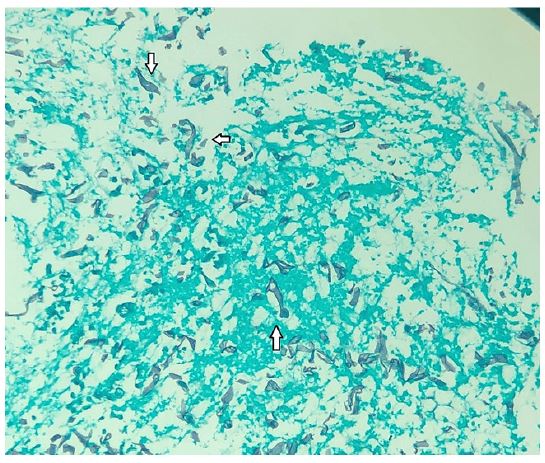

During his stay in the intensive care unit, he was treated with ceftriaxone and azithromycin, however his white blood cell count increased (Table 1), and clinical condition worsened, requiring an escalation of the antimicrobial spectrum to piperacillin and tazobactam (4,5 g qid) over the following two weeks, and later meropenem (1G tid) associated with teicoplanin (400 mg sid). In addition, the patient developed oliguria and renal dysfunction secondary to septic shock, requiring renal replacement therapy with hemodialysis. After 2 weeks in ICU, the patient developed upper gastrointestinal bleeding, with melena and a drop in hemoglobin. An upper digestive endoscopy was requested, which showed an ulceroinfiltrative lesion in the fundus and gastric body, measuring approximately 70 mm, and no signs of active bleeding and no need for endoscopic therapy (Figure 1). Biopsies of the lesion were performed, which demonstrated active, chronic ulcerated inflammation, with numerous short and irregular segments of hyphae amidst necrotic debris, without cellular atypicality, findings suggestive of mucormycosis (Figure 2).

Figure 1: Upper digestive endoscopy, demonstrating an infiltrative ulcer lesion, covered by fibrin, affecting the gastric fundus and great curvature of the gastric body.

Figure 2: Histology with Grocott-Gomori silver methenamine staining, demonstrating short and irregular segments of hyphae, amidst necrotic debris, Suggestive with Zygomycetes. Short and irregular segments of hyphae (arrows).